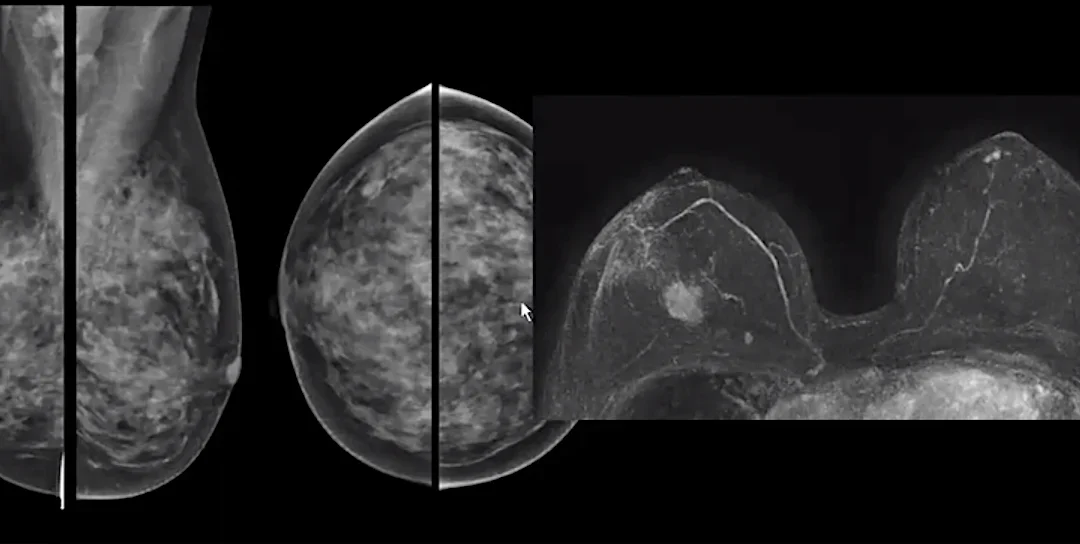

ΚΑΡΚΙΝΟΣ ΤΟΥ ΜΑΣΤΟΥ ΚΑΙ ΜΑΓΝΗΤΙΚΗ ΤΟΜΟΓΡΑΦΙΑ ΜΑΣΤΩΝ

Δεν είναι μόνο μια ροζ κορδέλα, δεν είναι μόνο ο ροζ φωτισμός κτιρίων και μνημείων, δεν είναι μόνο οι ομιλίες και οι διαλέξεις, δεν είναι μόνο ένας Οκτώβριος. Είναι το συνεχές μέλημα αυτοφροντίδας. Αυτό είναι και το μήνυμα των ημερών για τον καρκίνο του μαστού....